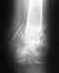

09.01.2010 получил травму - резаную рану в области основания большого пальца (между пальцем и ладонью), в результате которой был перерезан длинный сгибатель.

Через 6 часов была проведена операция, во время которой мне сделали дополнительный разрез в области запястья длиной 3см. для того, чтобы найти второй конец сухожилия, идущий со стороны мышцы. После операции наложили гипсовую лонгету для иммобилизации пальца на три недели. После снятия лонгеты в клинике мне посоветовали ежедневно разогревать руку в тёплой воде и делать активные и пассивные сгибания пальца. Палец до сих пор почти не в состоянии активно сгибаться (визуально -- 2-3 градуса). Пассивно сгибается почти нормально, всё ещё имеет небольшую отёчность. Ответьте, уважаемые хирурги, такое положение вещей считается нормальным? Каковы самые вероятные причины того, палец до сих пор не способен сгибаться? Есть ли надежда на то, что со временем работоспособность пальца полностью восстановится и если есть, то какие мероприятия мне нужно проводить для скорейшего выздоровления?Заранее благодарен за Ваши ответы